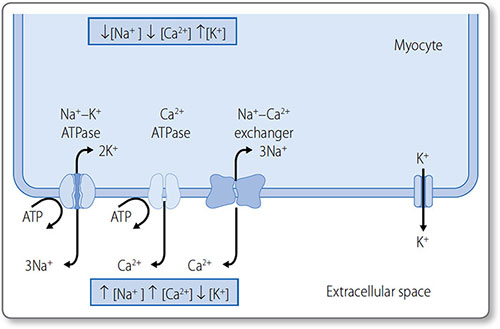

The main ions involved are the cations K+, Na+ and Ca2+ (Table 1.6):

Membrane-bound ion pumps actively pump K+, Na+ and Ca2+ out of the cell to make a small contribution to the RMP (Figure 1.21):

- Na+/K+-ATPase pumps three Na+ ions out of the cell and two K+ ions into the cell

- Ca2+-ATPase pumps Ca2+ out of the cell and into the sarcoplasmic reticulum

- The Na+–Ca2+ exchanger exchanges three Na+ ions for one Ca2+ ion.

Stage 2

The membrane is permeable to K+ but not other ions. K+ therefore passively diffuses out of the cell, down its concentration gradient, increasing the intracellular negative charge.

Stage 3

K+ efflux continues until equilibrium is reached between its concentration gradient and its electrochemical gradient. This equilibrium potential (E) is determined by ionic charge and the concentration gradient. For K+, EKis around –96 mV.

Figure 1.21: The resting membrane potential across the cardiomyocyte membrane. The three ion pumps (left) consume ATP to generate steep ionic concentration gradients. The membrane is permeable to K+ but less permeable to other ions. Therefore, K+ diffuses passively down its concentration gradient (right), leaving less positive charge (i.e. a net negative charge) on the inside of the cardiomyocyte.